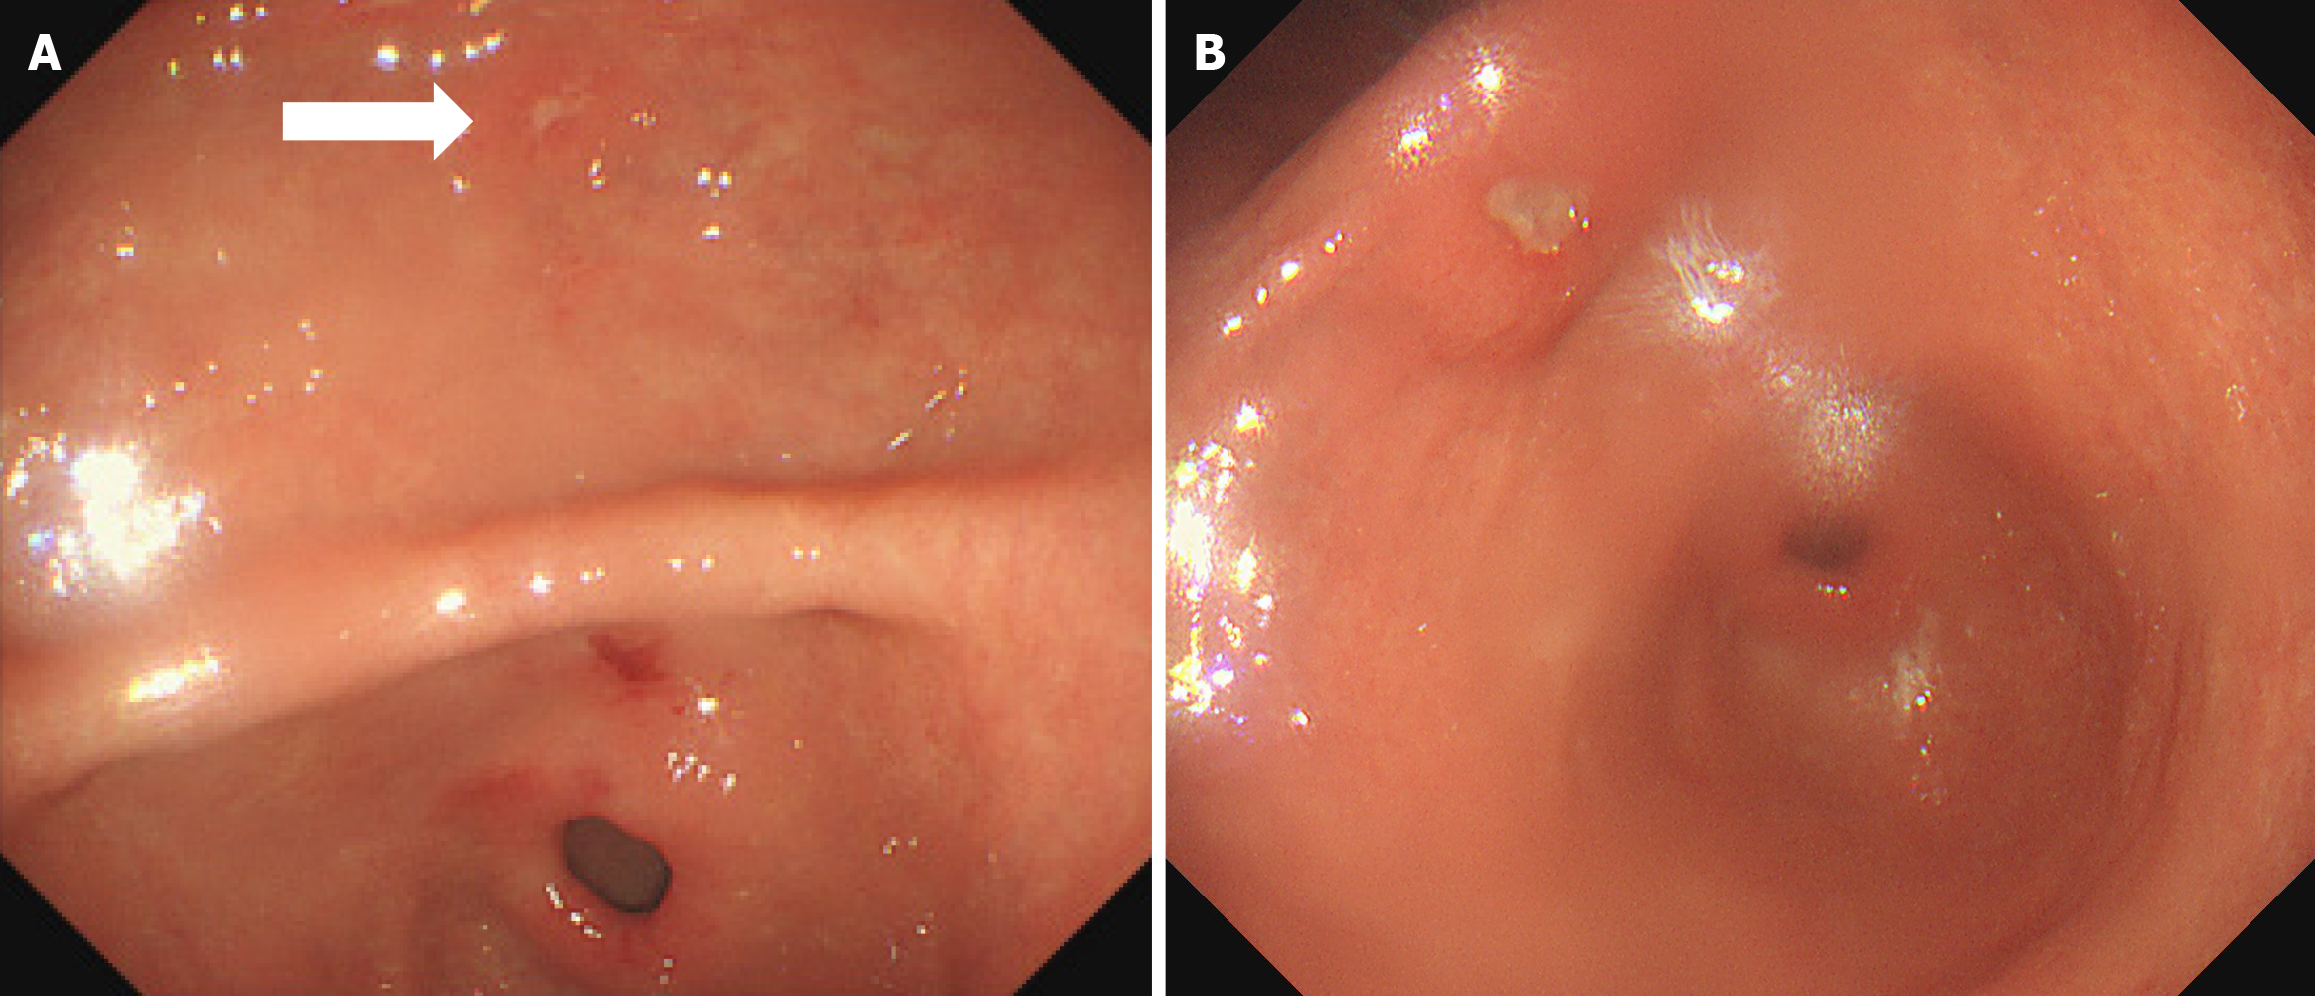

Figure 1 Endoscopic presentation of gastric antrum.

A: Multiple ulcers of the gastric antrum (white arrow) (2021-02-03); B: An ulcer on the small-curvature side of the antrum (2021-12-30).